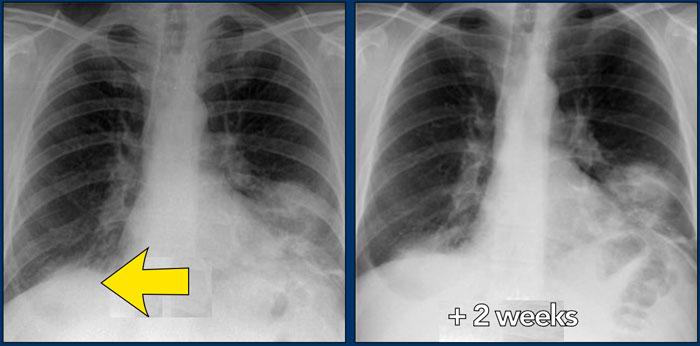

Bên trái là bệnh nhân nữ 47 tuổi với triệu chứng ho khan, khó thở nhẹ và xét nghiệm máu bình thường.

Bệnh nhân được chụp X-quang ngực và điều trị kháng sinh.

Phim kiểm tra được chụp lại do bệnh nhân không cải thiện.

Phim X-quang ngực đầu tiên cho thấy đông đặc hai bên ở thùy dưới (mũi tên), ban đầu được diễn giải là nhiễm trùng.

Sau hai tuần điều trị kháng sinh, không có cải thiện.

Chẩn đoán phân biệt lúc này bao gồm u ác tính (ung thư phế quản phế nang hoặc u lympho), viêm phổi tăng bạch cầu ái toan, viêm phổi tổ chức hóa, bệnh Wegener hoặc một thể không điển hình của sarcoidosis.

Tiếp tục với hình ảnh HRCT.

Có nhiều vùng đông đặc.

Các dấu hiệu kèm theo bao gồm hạch to rốn phổi và trung thất.

Chẩn đoán phân biệt trên hình ảnh CT về cơ bản giống như trên X-quang ngực.

Kết quả mô bệnh học xác nhận sarcoidosis phế nang.

Chỉ có một gợi ý duy nhất cho chẩn đoán, đó là sự hiện diện của các nốt nhỏ có thể nhận thấy ở hình 3, nhưng rất khó quan sát.

Trường hợp này minh họa rõ ràng rằng sarcoidosis thực sự là “kẻ bắt chước vĩ đại”.

Do đó, sarcoidosis cần được đưa vào danh sách chẩn đoán phân biệt của chúng ta!